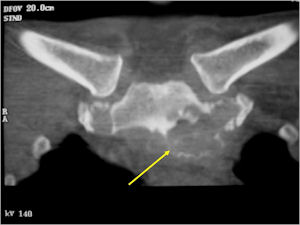

Plain X-rays:

- Geographic, circumscribed lesion usually around 5cm in size.

- There may be expansion of bone, cortical thinning and cortical breakthrough. A soft tissue mass may accompany this lesion but the soft tissue component is usually contained by the periosteum.

- The periosteum remains intact around the soft tissue component. Might need a CT scan to detect the subtle calcification (Egg Shell Rim of Calcification) associated with an intact periosteal reaction

- The lesion may be entirely radiolucent but usually shows some degree of mineralization. Mineralization may appear stippled like cartilage but do not see chondroid pathologically. Mineralization is sometimes better detected on a CT scan rather than an x-ray.

- Usually less surrounding sclerosis than an osteoid osteoma.

- Arise from the Diaphysis (75%) more commonly than Metaphyseal (25%)

- 4 cm to 6 cm in size